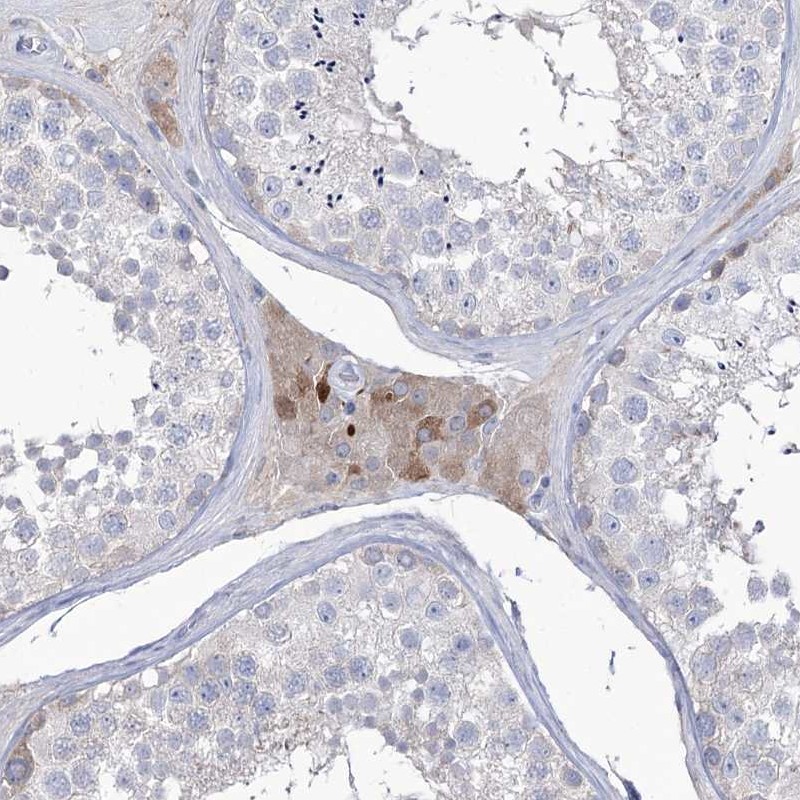

Immunohistochemical staining of human testis shows cytoplasmic positivity in Leydig cells.